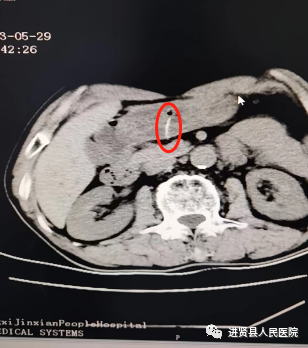

65岁的吴爷爷因事发2天前进食后出现上腹部疼痛,持续性隐痛后疼痛逐渐加剧来到医院急诊科,入院行CT检查示:胃腔内长条样高密度影,提示异物;由于“异物”进入位置比较深,副院长曾炳亮得知情况后立即联系省人民医院胃肠外科主任医师张伟及消化内科副主任医师龚志斌在急诊科进行会诊,并与进贤医院消化内科、普外科、胃镜室、麻醉科等多学科详细讨论如何把“异物”从胃内取出安全且创伤达到最小,在得到家属同意后,最后决定在龚志斌指导下,为患者行内镜下取出“异物”。